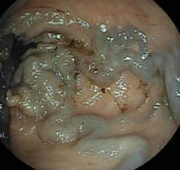

Κολονοσκόπηση. Ευδιάκριτα ευρήματα ισχαιμικής κολίτιδας (Ευγενική παραχώρηση Dr. V. Penopoulos)